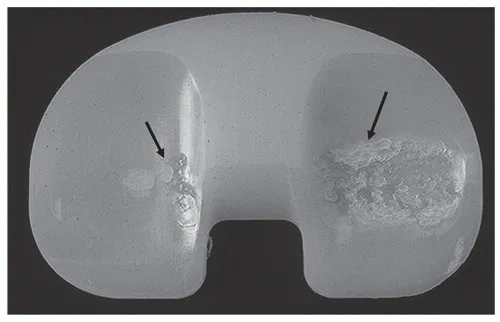

Implant Wear and Tear

Over time, joint implants can wear out, leading to pain, instability, and reduced function.